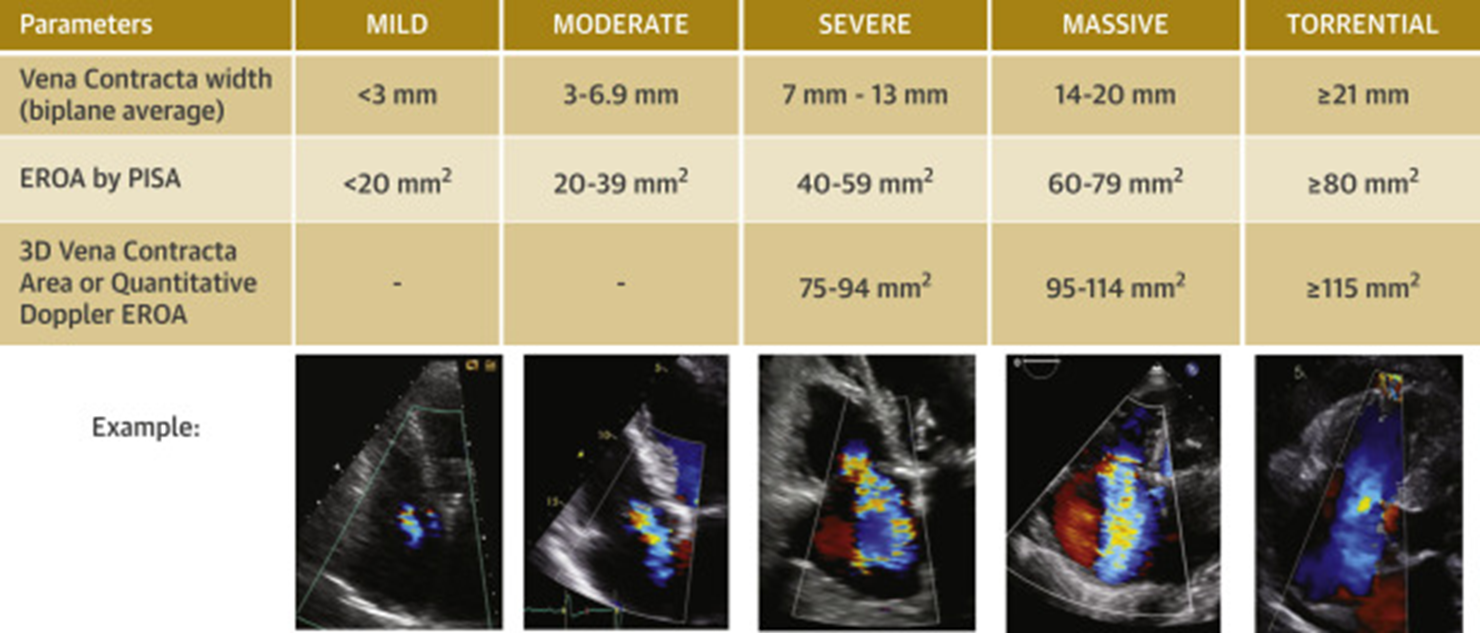

Quantification of TR